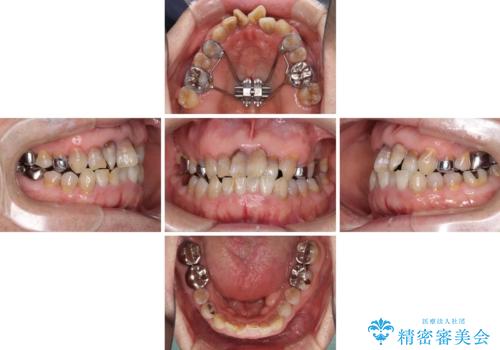

上顎の狭窄歯列 インビザラインによる拡大矯正

- 前歯の叢生と臼歯のクロスバイトを気にして来院された患者様です。

急速拡大装置による上顎の側方拡大を行い、その後はインビザラインより歯列を改善することとしました。

20代後半以降の男性は上顎骨の側方拡大処置の成功率が低く、今回も骨を拡大することができませんでした。

しかしながら、歯列を側方に拡大することができ、その後はインビザラインにて叢生を解消することができました。